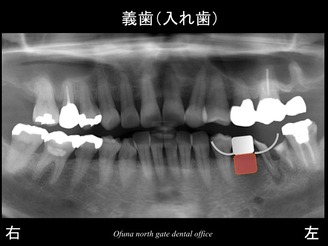

早速初診時のレントゲンから始めましょう!

初診時、下顎左側の奥歯が欠損しているため、治療法を聞きたく来院されました。

まずは、義歯(入れ歯)です。

義歯(入れ歯)の利点、欠点は以下のようになります。